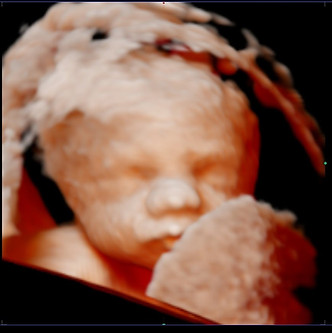

Een zwangerschap is en blijft een wonder. Dat heeft mij altijd al geïnteresseerd. Via opleidingen en stages heb ik veel ervaring opgedaan om je te kunnen laten genieten van de eerste mooie beelden van jouw ukkie.. Daarnaast heb ik ook een babyspa waar jouw kleintje kan genieten van een warm badje. Hier krijgen baby's weer hetzelfde gevoel als in de baarmoeder. Na het badderen kunnen ze ook genieten van een heerlijke babymassage.